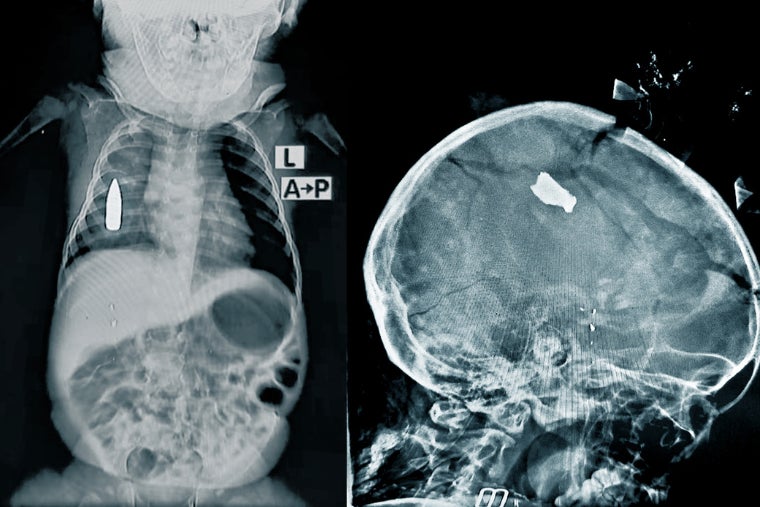

1歳8カ月の女の子は、爆発の破片で頭部を負傷して運ばれてきた。医療チームは慎重に女の子をレントゲン台に寝かせたが、小さな頭のもろい頭蓋のかけらが台の上に落ちた。モアイン医師は「このような症例が多いのです。あの女の子が助かったのは幸いです。助からない子どもたちもいました」と語る。

チームはリアドちゃんの止血に成功した。しかし、銃弾は胸に残ったままで、今後どのような処置ができるかは不明だ。